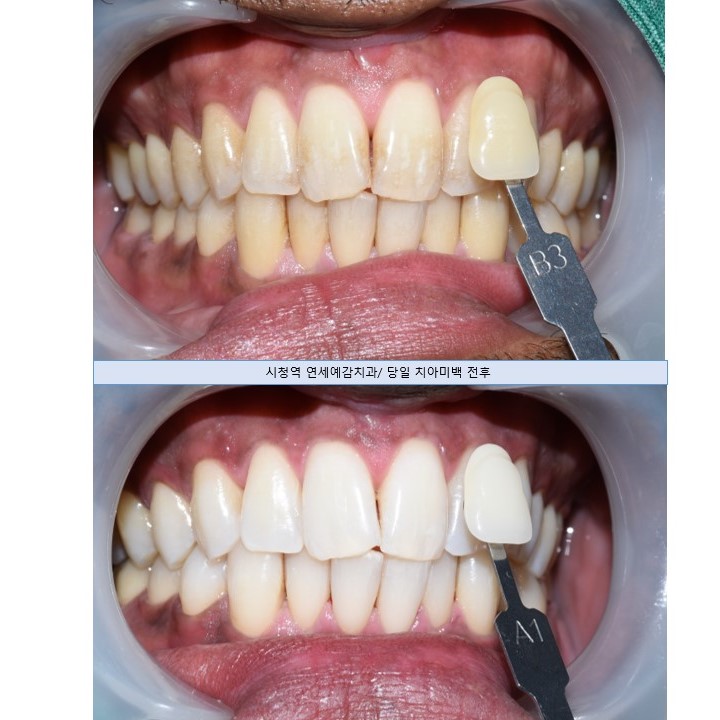

그 외에도 저희 치과에서 외국인들이 즐겨찾는 치과 치료 종목은 스케일링이나 미백인데요

연세예감치과가 외국인들에게 치아미백으로 유명해서

한국인들보다는 외국인들이 더 치아미백을 하러 많이 온답니다.